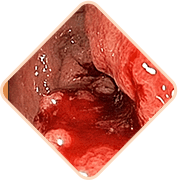

3 peligros mortales de hemorroides si no se trata a tiempo

Cualquiera de los siguientes puede ser

la causa de la muerte súbita del paciente!

Las heces contienen una cantidad gigantesca de gérmenes, bacterias y hongos. Si la infección ingresa al tejido pélvico y a los órganos vecinos, es posibleuna inflamación peligrosa y una infección de la sangre

Los vasos llenos del bulto hemorroidal son muy débiles. A menudo se rompen. El grado de pérdida de sangre en este caso puede ser tal que sea necesario transfusión de sangre

Se forman coágulos de sangre en los vasos. Estos coágulos de sangre pueden desprenderse y obstruir los vasos de los órganos internos, interrumpir la circulación sanguínea y causar un bloqueo en las arterias pulmonares.La probabilidad de muerte es alta.